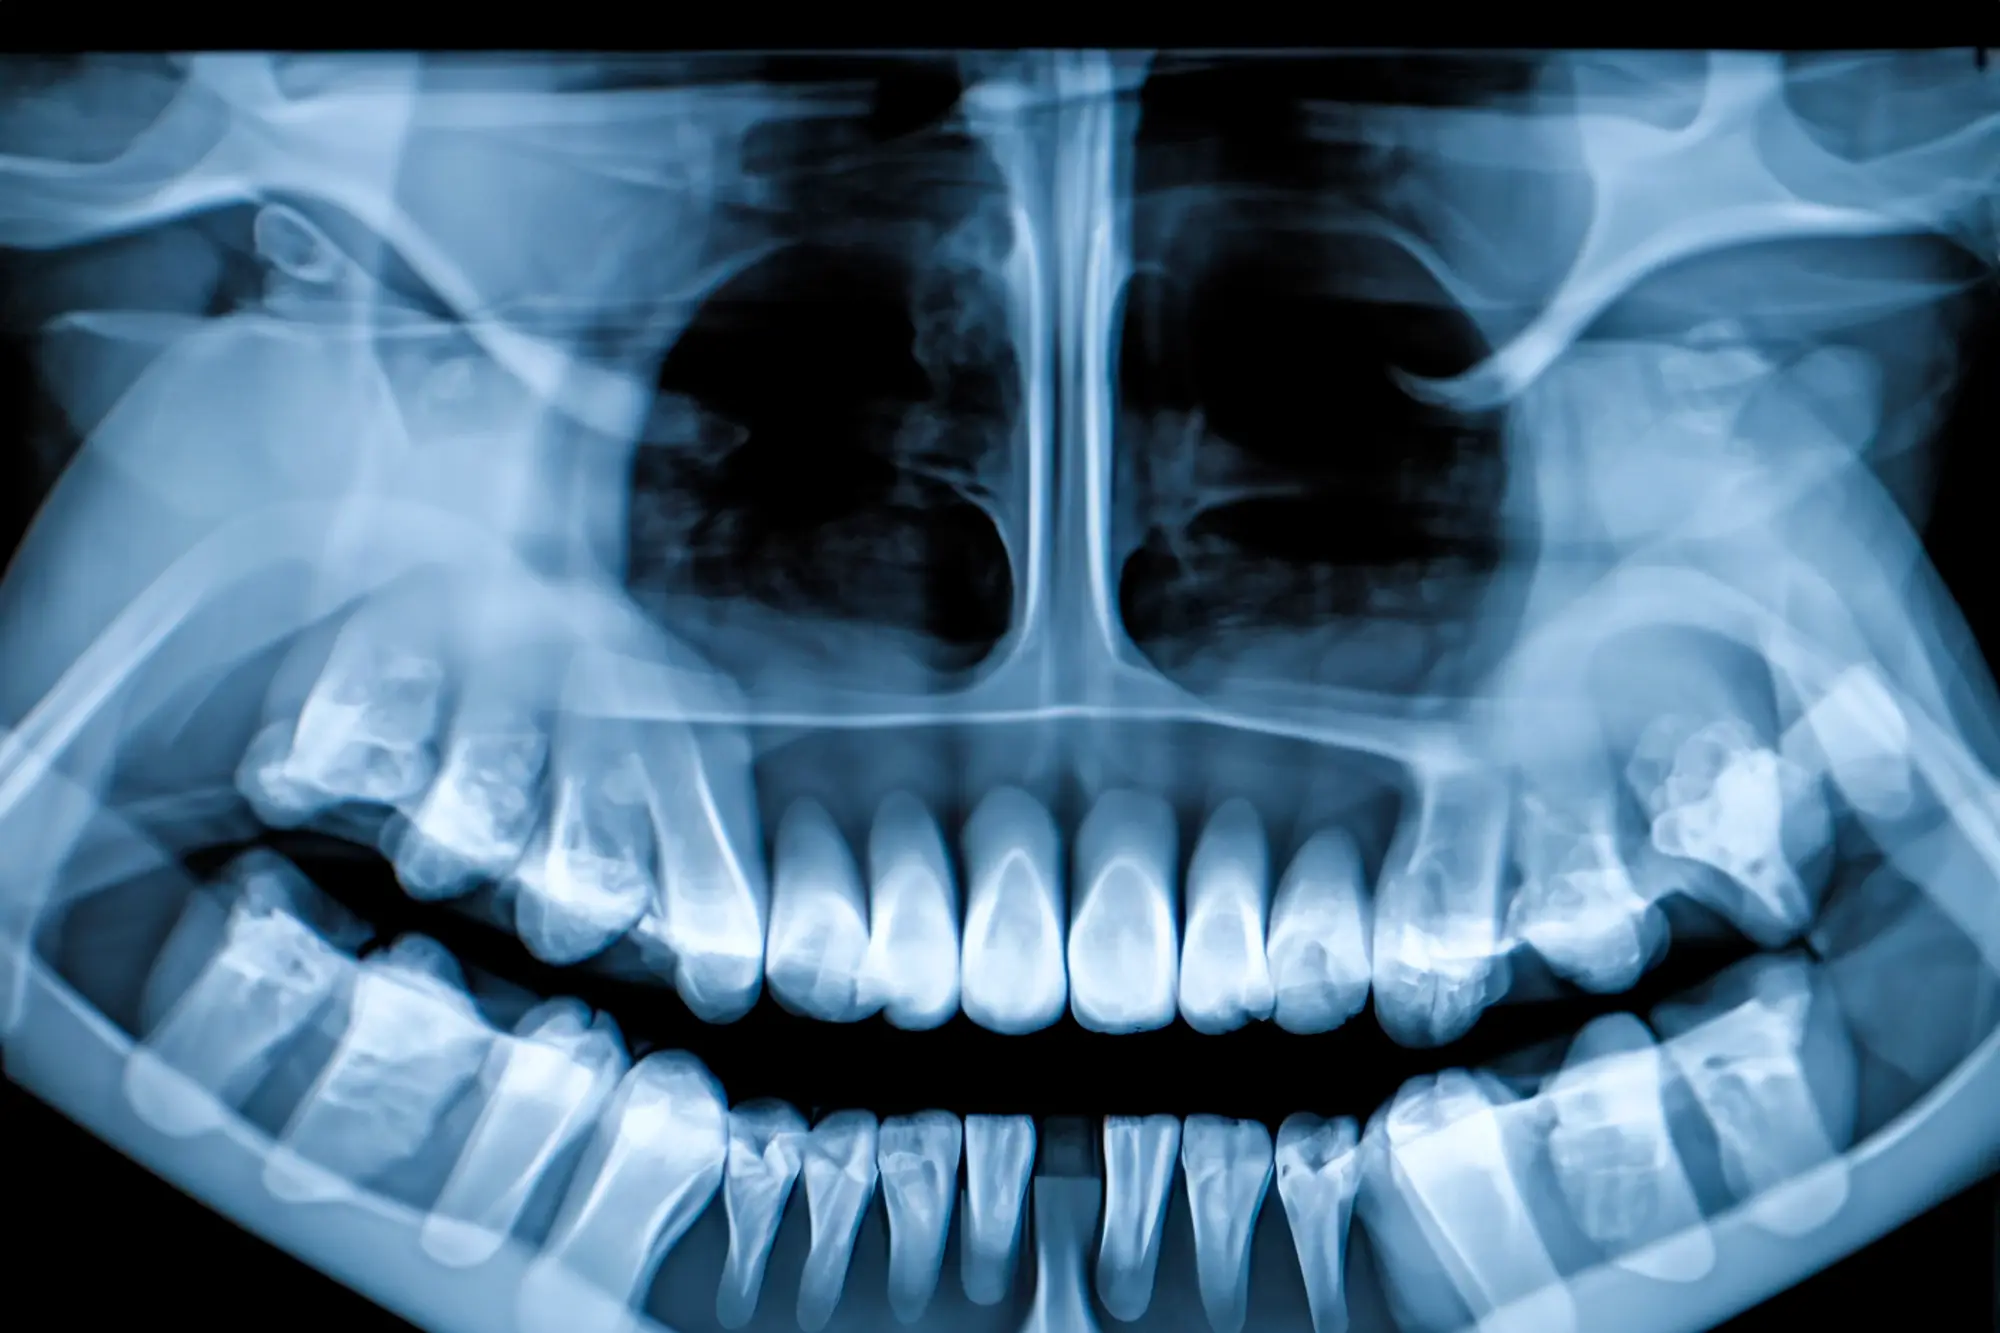

- Broken or cracked bones in the face, including the nose, cheekbones, or eye sockets

Bone Injuries

Facial bone fractures typically involve the cheekbones, nose or eye sockets. They affect the structure and function of the face, including breathing and chewing.

Complex fractures can also cause the bones to shift out of place, potentially affecting vision, breathing, or facial symmetry.